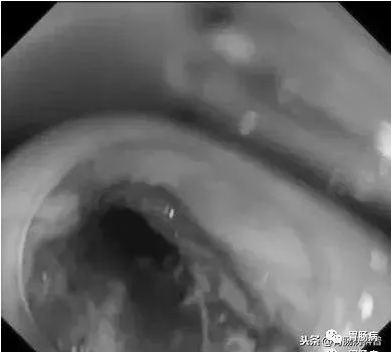

如下圖:

在食道入口,距門齒約18至20cm處可見片狀黏膜剝脫及條索狀裂傷,持續(xù)滲血。